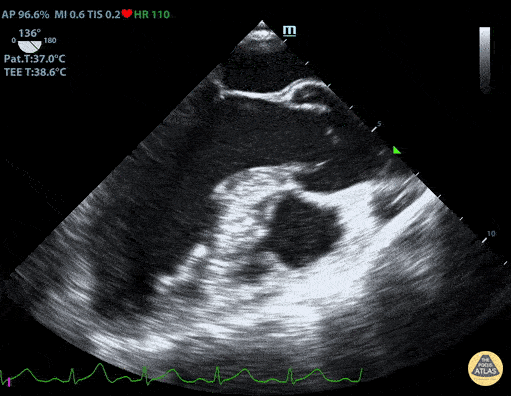

Normal Mid-Esophageal Long Axis View Duncan McGuire, DO, Emergency Medicine, Beaumont Health